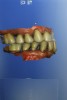

A 71-year-old man presented with acute pain in tooth No. 29 that was spontaneous, unresponsive to vitality testing, and sensitive to percussion. He was referred to an endodontist for treatment of acute apical periodontitis due to the non-vitality of the nerve. Because of the multiple restorations and lingual decay of the tooth, enamel and dentin were compromised, causing the tooth to be biomechanically at high risk and requiring an eventual post-and-core and crown (Figure 1 and Figure 2). Endodontic care included nonsurgical intracanal therapy and creating room for a post space.

Fig 2. Preoperative view of tooth to be restored shows defective Class 5 restoration that unfortunately was mirrored on the lingual gingival margin.

Figure 2